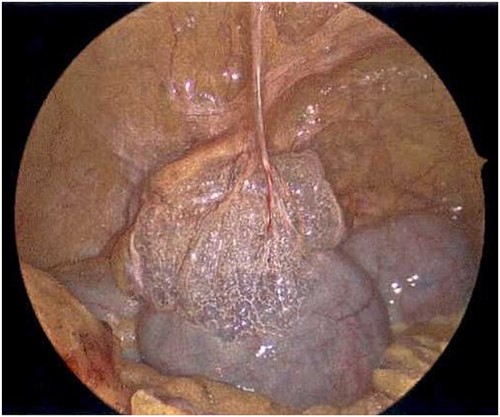

On Hospital Day 2, an interval CXR showed continued resolution of the right-sided pneumothorax but worsening subcutaneous emphysema of the bilateral chest wall and pneumoperitoneum (Fig. 3). Surgical consultation was sought, leading to diagnostic laparoscopy. In the abdomen, emphysematous changes within the gastrohepatic ligament and omental adhesions to the anterior abdominal wall were visualized (Figs 5 and 6). Laparoscopic exploration revealed no diaphragmatic injury or perforated viscera but identified emphysematous changes throughout the preperitoneal space, small and large bowel mesentery, and right paracolic gutter (Figs 7 and 8). Immediate post-op CXR no longer showed evidence of pneumoperitoneum (Fig. 4). The patient was transferred back to the ICU and extubated after three days on Day 5. After the removal of chest tube and transfer to a medical floor on Day 8, the patient developed aspiration pneumonia that was treated with antibiotics. She was discharged on Day 15.

Laparoscope of the anterior abdominal wall revealing emphysematous changes within the preperitoneal space.